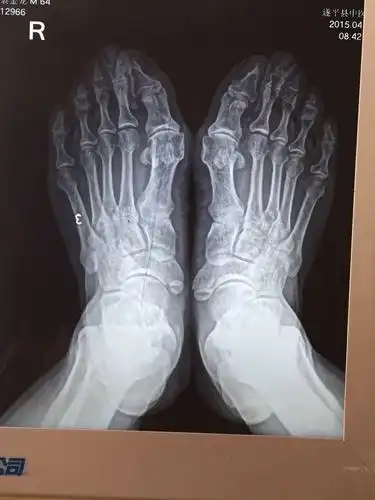

18岁女孩和妈妈都是大脚骨,是遗传吗,怎么治?骨科老牛来支招!

做了大脚骨手术一年又复发了手术失败原因竟然是这个

拇外翻大脚骨手术矫治术